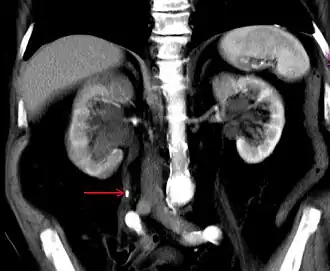

Der klinischen Untersuchung ist der Harnleiter kaum zugänglich, auch auf einer normalen Röntgenaufnahme stellt er sich nicht dar, lediglich röntgendichte Harnleitersteine werden abgebildet. Deshalb werden bei der Urografie meist intravenös verabreichte Kontrastmittel verwendet. Diese werden über die Niere ausgeschieden, gelangen so in die Harnleiter und kontrastieren diese. Hiermit lässt sich der Harnleiter in seiner gesamten Länge darstellen. Die Urografie ist, nicht zuletzt wegen der Gefahr von Nierenschädigungen, durch andere bildgebende Verfahren weitestgehend ersetzt worden und wird heute vor allem noch zur Diagnostik von Harnleitersteinen angewendet. Die Darstellung des Harnleiters mittels Ultraschall gelingt meistens nur bei Stauungen (Ureterozele). Die Computertomografie (CT) wird in Niedrigdosistechnik oder als CT-Urografie, also mit Kontrastmittelverabreichung eingesetzt. Sie ist im Nachweis von Harnleitersteinen verlässlicher als die herkömmliche Urografie und kann auch zur Klassifikation und Stadienbestimmung in der Onkologie verwendet werden. Die Magnetresonanztomographie (MRT) hat eine ähnliche diagnostische Aussagekraft und ist besonders dann angezeigt, wenn eine Kontrastmittelgabe wegen Unverträglichkeit nicht möglich ist.[50]

Mit einem Miktionszystourethrogramm kann ein krankhafter Rückfluss von Urin von der Blase in die Harnleiter und die Niere dargestellt werden. Die Ureteroskopie ist ein endoskopisches Verfahren zur direkten bildlichen Darstellung des Lumens und gegebenenfalls auch zur Behandlung (minimalinvasive Chirurgie) bestimmter Harnleitererkrankungen wie Steinen. Das Endoskop kann dabei entweder über die unteren Harnwege (retrograde Ureteroskopie) oder, wenn dies aufgrund von Verlegungen nicht möglich ist, durch die Bauchdecke und das Nierenbecken in den jeweiligen Harnleiter eingeführt werden (antegrade Ureteroskopie).[51] Die Ureteroskopie ist besonders bei Steinen[52] sowie bei Tumoren diagnostisches Mittel der Wahl, allerdings sind bei Tumoren zur Begutachtung der Umgebung (insbesondere der Lymphknoten in Hinblick auf Metastasen) zusätzlich CT- oder MRT-Untersuchungen notwendig.[53]

Die häufigste Ursache für Verlegungen des Harnleiters sind Harnleitersteine.[74] Da die Passage des Urins durch den Harnleiter relativ rasch verläuft, entstehen Harnleitersteine meist im Bereich der Niere als Nierenstein und verkeilen sich dann bei der Passage im Harnleiter. Harnleitersteine können nach Art ihrer Entstehung verschiedene chemische Zusammensetzungen haben.[75] In den Industrieländern beträgt die Inzidenz von Harnsteinen etwa 10 %, mit steigender Tendenz.[74] Auch bei Hunden und Katzen sind Harnsteine die häufigste Ursache für Harnleiterobstruktionen,[76] aber prinzipiell können alle Tierarten betroffen sein. Es gibt Fallberichte zu Pferden,[77] Kaninchen,[78] Meerschweinchen,[79] Zwergottern,[80] Delfinen[81] und Vögeln[82]. Durch krampfartige Muskelaktionen versucht der Harnleiter, die Steine weiter zu transportieren, was als schmerzhafte Harnleiter-Kolik wahrgenommen wird. Die wehenartigen heftigen Schmerzen strahlen je nach Lokalisation des Steins in den Rücken, den Bauch, die Leiste oder die Genitalien aus. Häufig kommt es auch zu Blutbeimengungen im Urin (Mikrohämaturie oder Makrohämaturie).[74] Bei erschwertem Abfluss hypertrophiert die Uretermuskulatur oberhalb des Hindernisses rasch. Die Steine werden heute vor allem ureteroskopisch bzw. antegrad ureteroskopisch mittels Laser-Lithotripsie oder von außen mittels extrakorporaler Stoßwellenlithotripsie zertrümmert.[83] Führt dies nicht zum Erfolg, muss der Stein durch Eröffnung des Harnleiters (Ureterolithotomie) entfernt werden, die heute vor allem laparoskopisch erfolgt.[84] Hier besteht anschließend immer die Gefahr der Entstehung von narbigen Einengungen (Strikturen), weshalb meist auch eine Harnleiterschienung durchgeführt wird.[85] Harnleiterschienen werden auch bei Harnleiterstrikturen anderer Ursache oder bei Nierensteinen eingesetzt.[86]